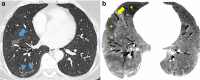

Medical imaging methods are assuming a greater role in the workup of patients with COVID-19, mainly in relation to the primary manifestation of pulmonary disease and the tissue distribution of the angiotensin-converting-enzyme 2 (ACE 2) receptor. However, the field is so new that no consensus view has emerged guiding clinical decisions to employ imaging procedures such as radiography, computer tomography (CT), positron emission tomography (PET), and magnetic resonance imaging, and in what measure the risk of exposure of staff to possible infection could be justified by the knowledge gained. The insensitivity of current RT-PCR methods for positive diagnosis is part of the rationale for resorting to imaging procedures. While CT is more sensitive than genetic testing in hospitalized patients, positive findings of ground glass opacities depend on the disease stage. There is sparse reporting on PET/CT with [18F]-FDG in COVID-19, but available results are congruent with the earlier literature on viral pneumonias. There is a high incidence of cerebral findings in COVID-19, and likewise evidence of gastrointestinal involvement. Artificial intelligence, notably machine learning is emerging as an effective method for diagnostic image analysis, with performance in the discriminative diagnosis of diagnosis of COVID-19 pneumonia comparable to that of human practitioners.